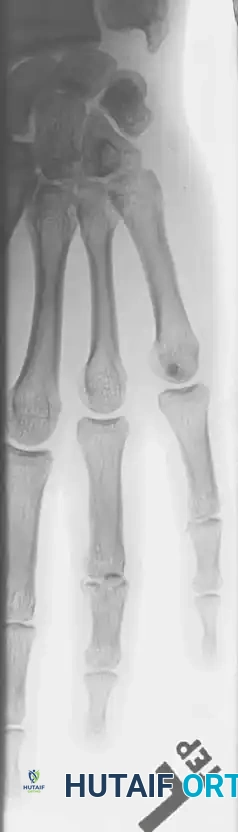

Fracture-Dislocations of the Proximal Interphalangeal (PIP) Joint

Fracture-dislocations at the PIP joint typically result in an unstable dorsal displacement of the middle phalanx. This is caused by the disruption of the volar plate's attachment to the volar lip of the middle phalanx, often accompanied by impaction of the articular surface.

Treatment is strictly dictated by the percentage of articular surface involved and the degree of comminution.

1. Large Volar Fragment (>50% of Joint Surface)

If a large, single volar fragment involving more than 50% of the joint surface is present, the joint is highly unstable. Open reduction and internal fixation (ORIF) is required. This can be achieved with miniature lag screws, K-wires, or a wire loop pull-out technique to secure the fragment and restore the volar buttress.